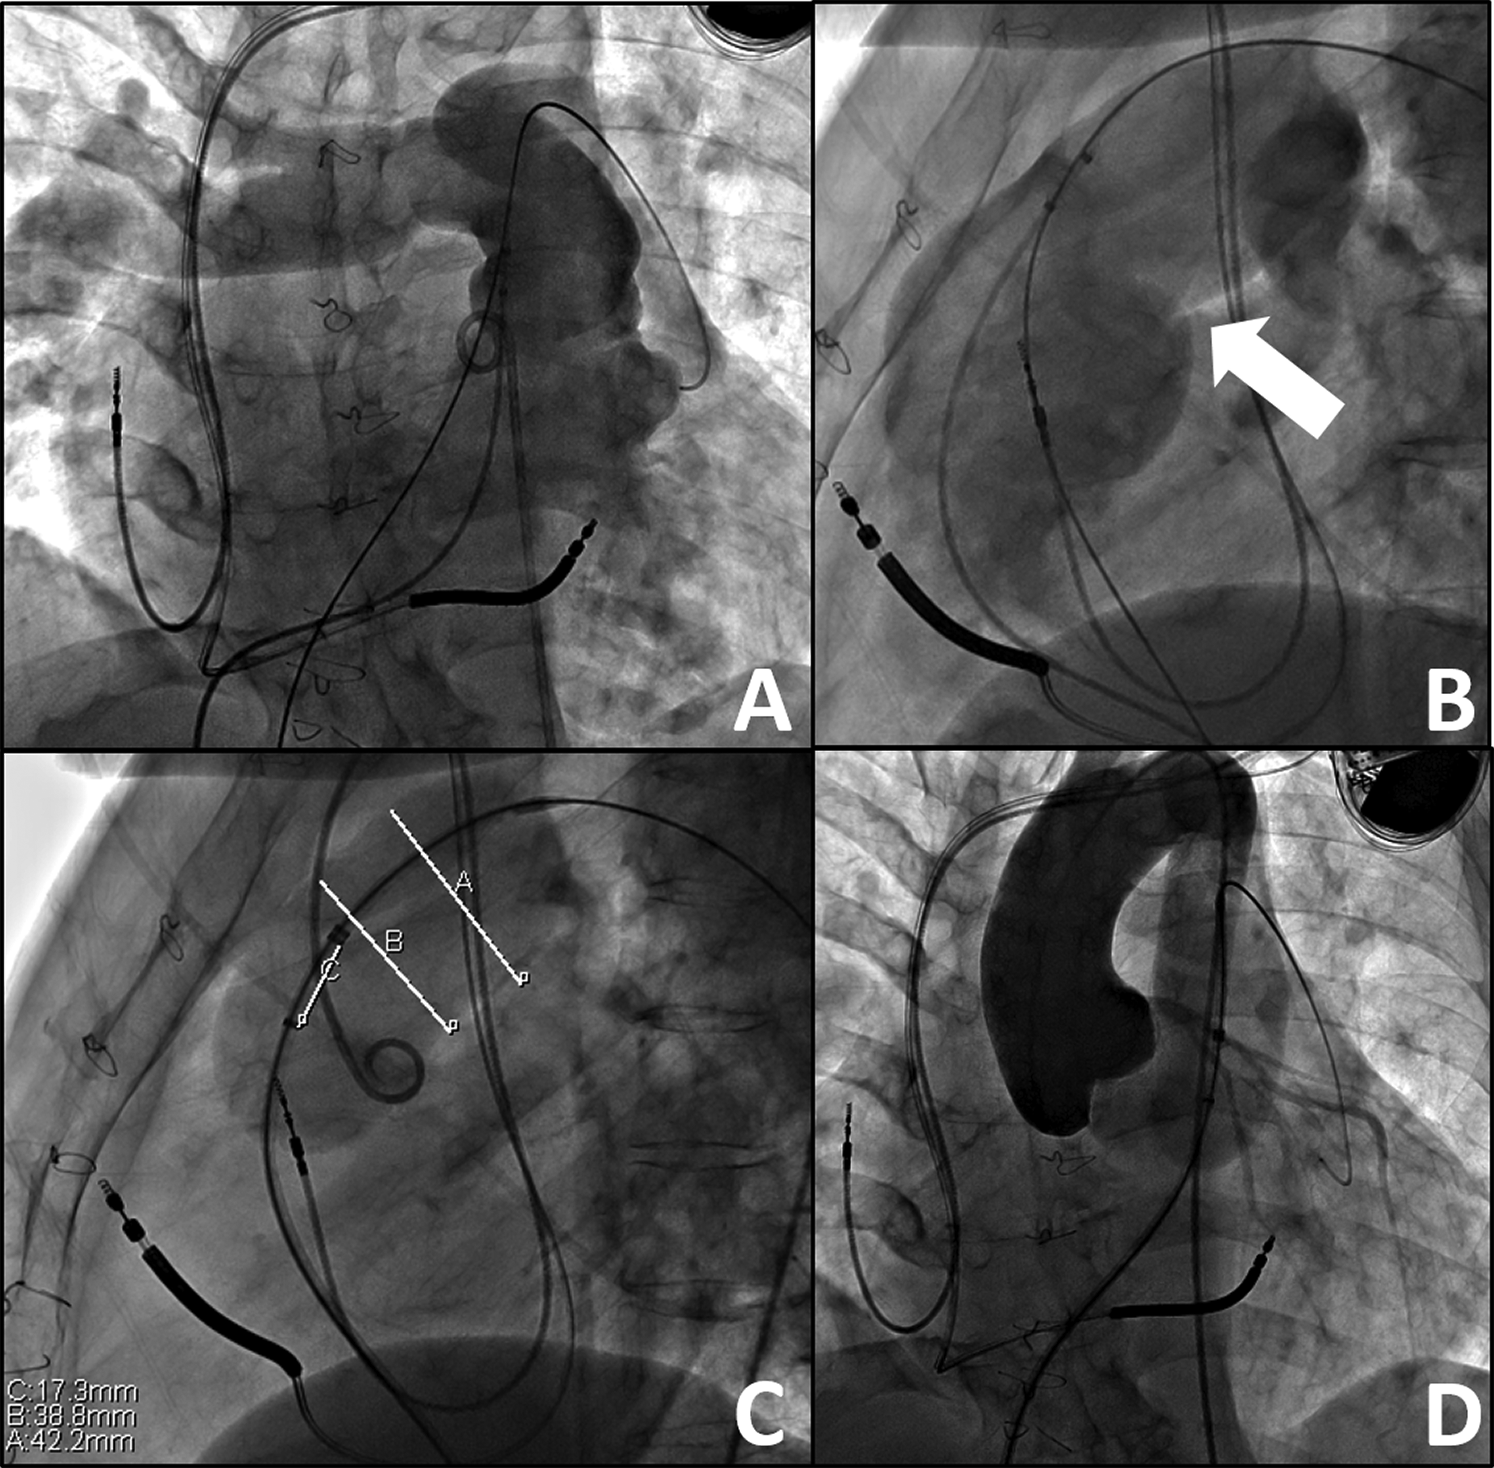

Hybrid PVR entailed off-pump RVOT-PA plication with subsequent transcatheter PVR occurring during the same procedure. All procedures were performed in a hybrid catheterization suite under general anesthesia. A femoral venous catheter was advanced to a distal PA branch. Full median sternotomy was then performed to expose the main PA, with minimal dissection of the heart and aorta. RVOT angiography was performed to obtain a roadmap of the anatomy with the open chest. An approximate measurement of the main PA was made to assist in determining the appropriate extent of plication (Fig. 1). Main PA/RVOT plication was performed with multiple pledgeted horizontal mattress sutures to provide an elongated, waist-like reduction of the selected landing zone. If there was calcification of a preexisting RVOT patch, a mattress suture, usually 4.0 Prolene (Ethicon, Somerville, NJ), was used to provide focal narrowing of the RVOT to approximately the required minimal diameter for the planned transcatheter device. Circumferential dissection of the main PA was not required. Following completion of mPA/RVOT plication, repeat RVOT angiography and balloon sizing was performed to re-assess the anatomy of the landing zone and ensure that a diameter suitable for a transcatheter valve was achieved (Fig. 2). If the post-plication diameter was still too large for the valve, then further plication was performed. If clinically indicated for the valve system (e.g., - Melody PVR, small conduits/RVOT < 24 mm, etc.), the main PA was pre-stented to create a landing zone for the valve construct and delivered via either femoral vein. In one patient, the delivery system could not be advanced from the femoral approach to the landing zone due to alteration in angle following RV plication. The valve was successfully delivered via a direct PA insertion. After deployment of a valve, the function of the valve was assessed by angiography and transthoracic echocardiography.

Figure 1: Baseline Angiography, prior to Hybrid Intervention. A) Anteroposterior view of a right ventriculogram with distal wire in the distal left pulmonary artery. B) Lateral view of the large right ventricular outflow tract with a landing zone (white arrow) too large for transcatheter valve placement. C) Balloon sizing of the right ventricular outflow tract demonstrating measurements too large for current transcatheter valve systems, narrowest portion being 38.8 mm during balloon sizing. D) Coronary artery compression testing via aortogram during balloon sizing of the right ventricular outflow tract–no concerns for coronary artery insult or pathology